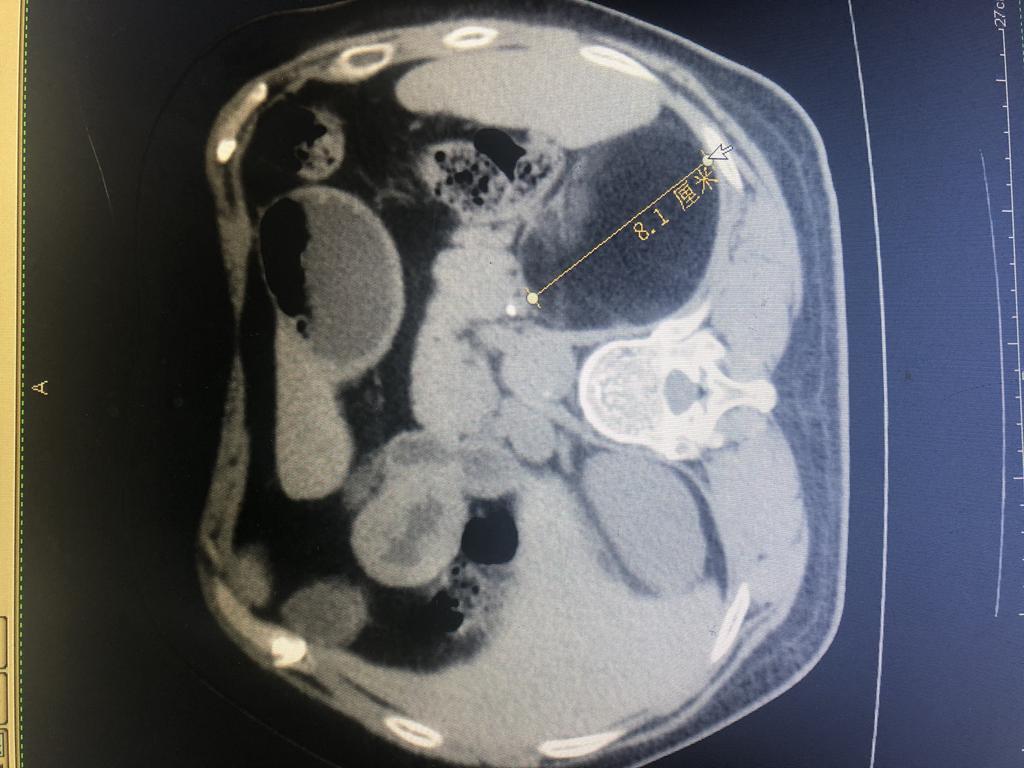

患者,女性,61岁,在乡镇医院体检发现左肾上腺有1个8×9cm巨大包块,遂来崇州市人民医院就诊后入泌尿外科住院治疗。因该患者左肾上腺包块大,泌尿外科主任杨华、副主任医师徐浩、医师彭思洋对患者的身体基础情况和病情进行反复评估,决定采取经腹入路行微创手术治疗。

肿瘤CT

6月17日,由徐浩主刀,在全麻下为该患者行经腹入路腹腔镜下左肾上腺包块切除术。术后患者情况良好,目前已康复出院。